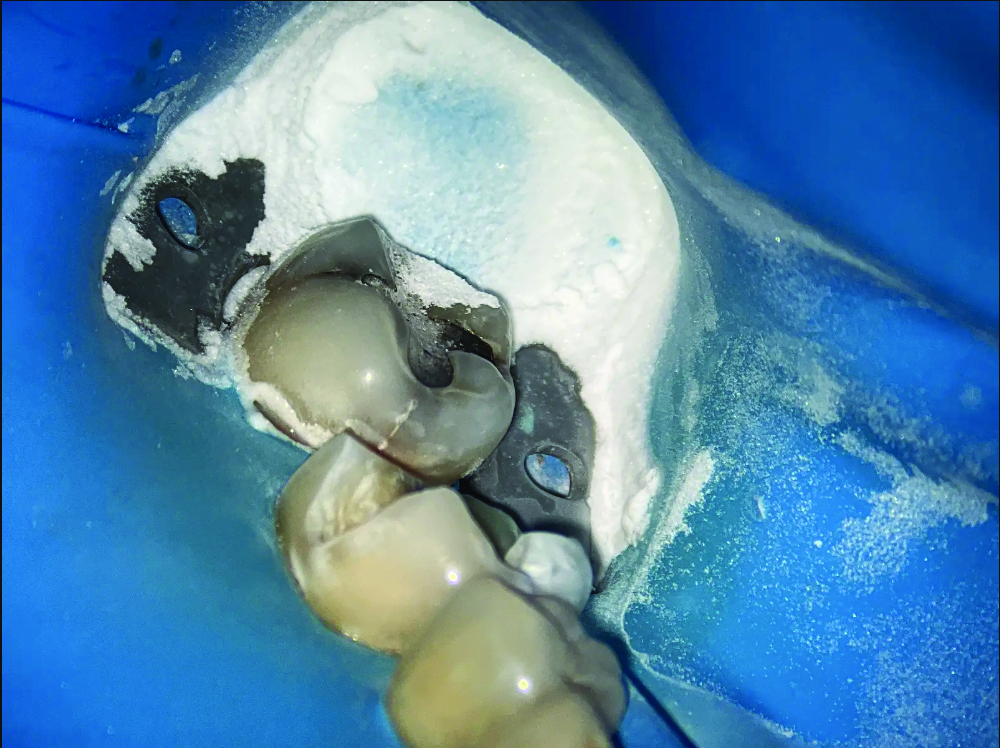

Over the years, air abrasion has continued to evolve, but aluminum oxide remains one of the most reliable abrasives used in practice today. Although alternatives such as bioactive glass have been explored, aluminum oxide is still the preferred choice because of its hardness and consistent cutting ability, especially when working on enamel and dentin.11 Unfortunately, the fine particles released during air abrasion can become airborne, posing risks such as soft-tissue irritation or inhalation. To address concerns related to airborne particles, newer air abrasion devices have been developed with water spray functions. These improvements help reduce the amount of dust and debris floating around in the air. In addition, the water stream makes the abrasive jet more visible, which helps the operator accurately follow its direction and point of contact. Furthermore, the addition of water helps to prevent excessive heat buildup in the tooth. Despite these advancements, it is still crucial to use isolation techniques, such as rubber dams, and to rely on high-volume suction to keep the work area clean and safe (Figure 4 and Figure 5).

(4.) Intraoral images of a lower first molar before and after air abrasion to create a biobase. The accumulated aluminum oxide particles highlights the amount of abrasive used and the necessity of a rubber dam to prevent them from being inhaled or spread in the mouth.

Figure 4

(5.) Intraoral images of a lower first molar before and after air abrasion to create a biobase. The accumulated aluminum oxide particles highlights the amount of abrasive used and the necessity of a rubber dam to prevent them from being inhaled or spread in the mouth.

Figure 5